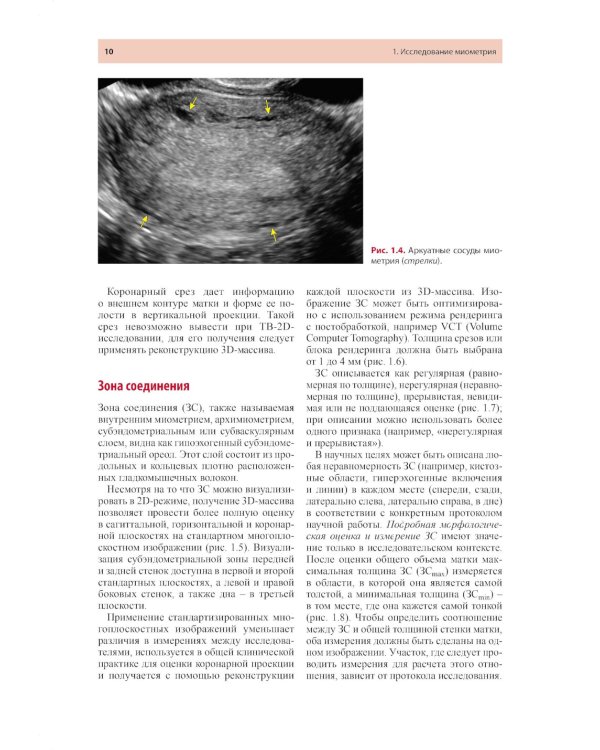

Книга является адаптированным переводом консенсусов международных групп экспертов ультразвуковой диагностики в гинекологии, таких как Morphological Uterus Sonographic Assessment (MUSA) и International Endometrial Tumor Analysis (IETA) с авторскими комментариями. Подробно описан протокол исследования миометрия и эндометрия по международным стандартам, представлены эхографические признаки опухолей миометрия и аденомиоза. Книга будет полезна как опытным, так и начинающим врачам ультразвуковой диагностики, акушерам-гинекологам, онкологам, репродуктологам, аспирантам и ординаторам.| Издательство | МЕДпресс-информ |